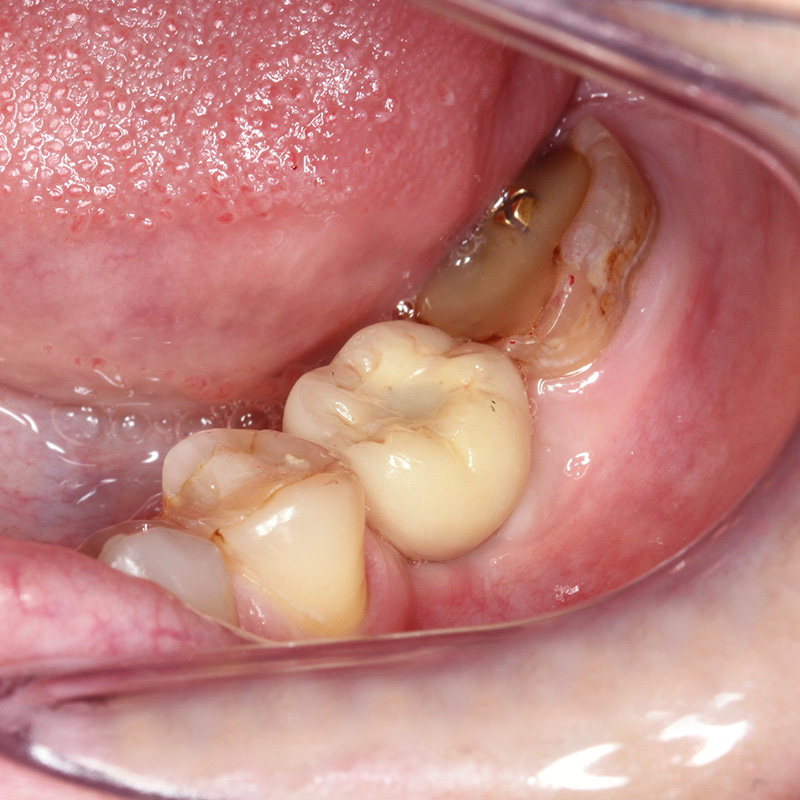

Удаление зуба в результате хронического периодонтита с одномоментным проведением имплантацииСмотреть работуСрок лечения:60 минутСумма лечения:74 970 руб.